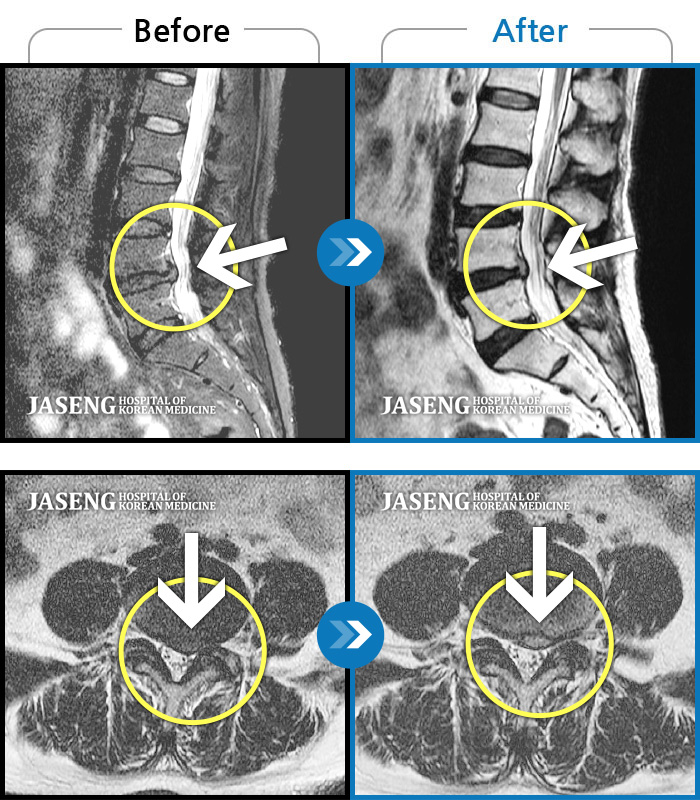

허리디스크

인천 · 강아현 원장

물건을 들다 삐끗한 후 발생한 허리 통증 및 하지 방사통, 하지 감각 저하 및 근력 저하 발생

촬영시기

2025.03.04 ~ 2025.09.10

2025.09.22

조회수 248